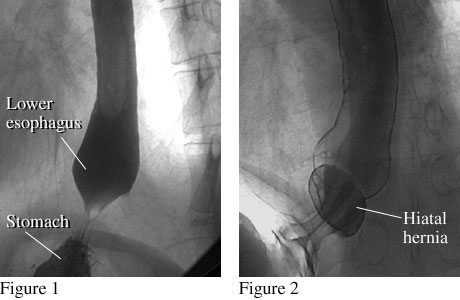

Barium Swallow Pictures